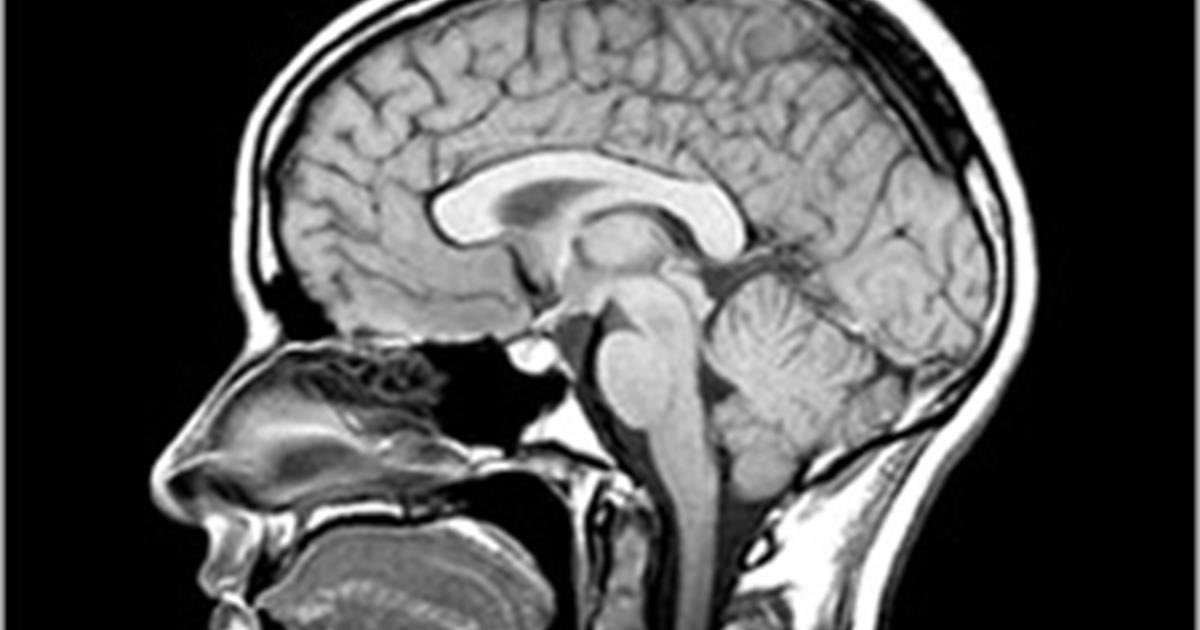

بدأت في كونها عصبية وتنفعل وتنفجر لأتفه الاسباب. أصبح التعامل معها صعب. حتى حبيبها لم يعد يستطع التعامل معها لكمية الوسوسة والانفعالات والتهجم الذي يبدر منها. وفي أحد الليالي اكتشف انها تصاب بتشنج فتم نقلها للمستشفى. لم تظهر فحوصات الدم و الاشعة المغناطيسية او تخطيط المخ أي مشكلة

راجع حميع التحاليل التي تم عملها والاشعة المقطعية والرأسية وتخطيط المخ وفحوصات المناعة والالتهابات ولم يجد مايعينه على تشخيص إكلينيكي.

طلب بعدها تحليل للنخاع الشوكي ليأكد شكوكه وكانت إيجابية. كانت سوزانه كالهان مصابة بإلتهاب الدماغ وهو مرض يصيب الدماغ كله او جزء منه كما في حالتها عند التعرض لالتهابات سابقة، في حالتها الانفلونزا. كان نصف الدماغ حرفيا "يحترق On fire” ولهذا نصف الدماغ السليم اظهر الرسمة بذاك الشكل

كتبت سوزانه كتابها "brain on fire" "دماغ يحترق" الذي يسرد معاناتاها النفسية والجسدية جراء التهاب الدماغ encephalitis. اصبح متصدر الكتب المباعه في امريكيا ومنه اقتبستت قصة الفيلم الذي اخذ نفس الاسم brain on fire والذي اطلق في عام ٢٠١٦.